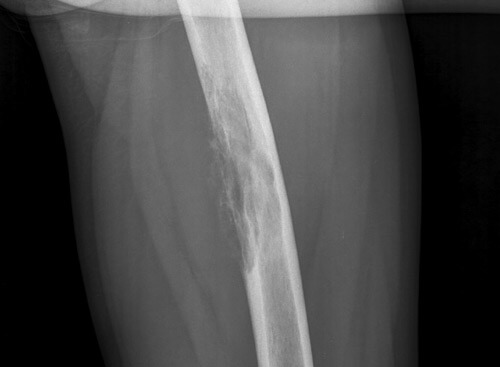

Острое воспаление надкостницы может быть диагностировано на основании анамнеза и симптомов, так как рентгенологическое исследование покажет патологическое изменение надкостницы только через 2 недели с начала заболевания. Главным методом диагностики рассматриваемого заболевания является рентгенография, которая позволяет оценить форму, структуру, очертания, размеры и распространенность наслоений в надкостнице. Но рентгенография позволяет врачу составить только лишь представление о характере, форме заболевания, но не дает возможности выяснить истинную причину прогрессирующей патологии. Чтобы диагностика была полноценной, пациенту назначают: